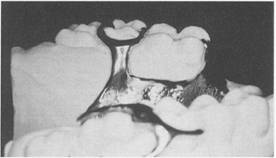

Fig. 5-34 Maxillary Class I partial denture frame­work with anatomic replica palatal major connector. Although retention is increased by using broad major connector, need for indirect retainers still exists, and they are placed on mesio-occlusal surfaces of first premolars. Direct retention is furnished by bar-type clasps engaging distobuccal undercuts on second premolars. Metal extension from framework contacts prepared guiding planes on distal surfaces of second premolars to complete clasp assembly.